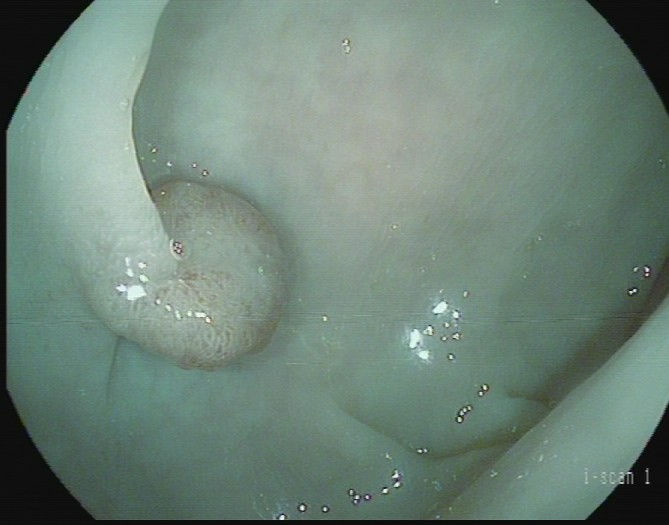

(1)赖女士(62岁,横结肠息肉,图1)

肠镜一照,息肉现形!形态各异的大肠息肉,离癌有多远?(图1)

图1

病理诊断:管状腺瘤,伴低级别上皮内瘤变。

解读:管状腺瘤是最常见的腺瘤性息肉。低级别上皮内瘤变意味着腺体结构和细胞出现了轻度到中度的异常改变,是明确的癌前状态。此阶段积极切除并定期复查,可有效阻断癌变进程。距离癌:一步之遥,癌前病变中期。